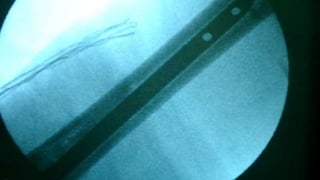

Distal Femur retrograde nailing

Brief steps of distal femoral retrograde nailing of femur